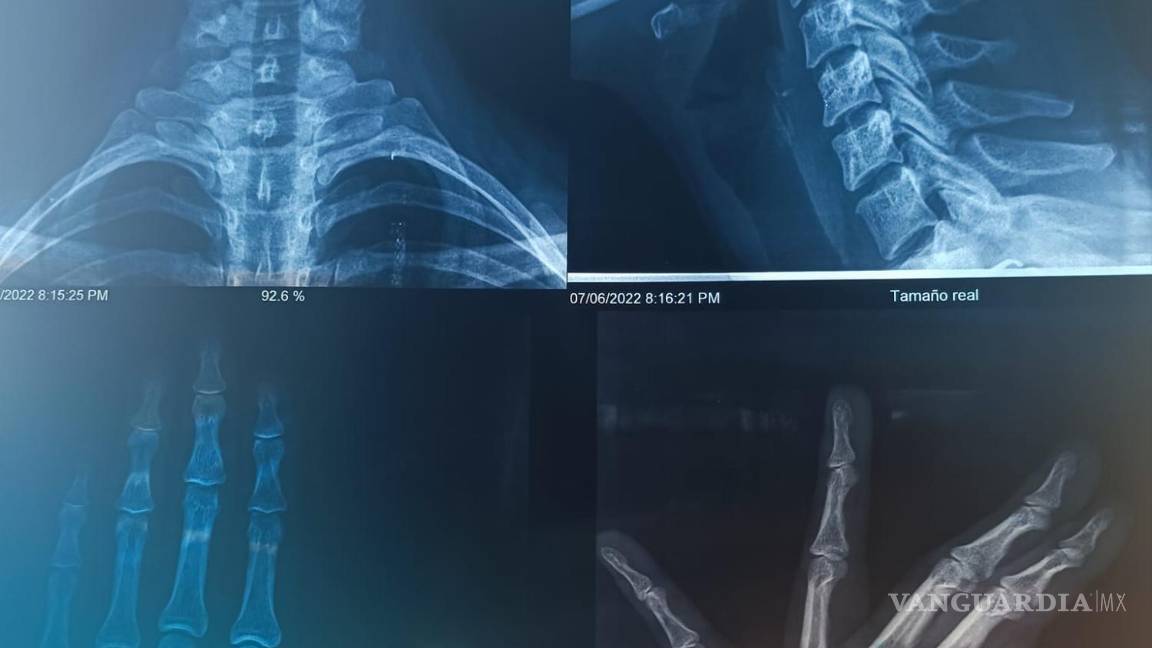

“Una prima mía y su esposo se subieron a mi coche y me comenzaron a golpear, dejándome diferentes lesiones que son las que se pueden ver en las fotos.

“La cosa llegó a tanto, que me golpearon en la nariz, cosa que hacía que yo batallara para respirar. Aparte que el esguince en el cuello me complicaba las cosas, hasta para comer”, expresó Alexa.

Con base al testimonio, declaró que la agredieron haciendo uso de cinturones y cadenas en las manos, lo que infligió más daño y causó lesiones severas que se vieron reflejadas durante la revisión médica de la víctima, además de esguinces en los dedos y torceduras en la nariz.

$!Imagenes de las radiografías de Alexa.